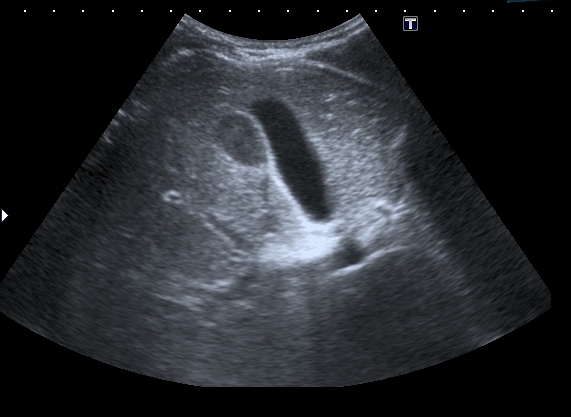

На УЗИ рядом с желчным пузырём определяется овоидное образование солидной струкутры с чёткими контурами.

Была такая мысль, но очень уж разнится по структуре это образование от самого желчного пузыря. В динамичном изображении не было перехода полости желчного пузыря в образование. И чёткой стенки не было на всём протяжении...Dr Alex писал(а):Похоже на перегиб по типу "колпака", только он внизу а не сверху

Полазил в сети на предмет удвоения желчного пузыря. Ультразвуковая картина значительно зависит от уровня, степени удвоения и оттока желчи из удвоенной части желчевыводящей системы. Вероятно в моём случае могло быть фундальное удвоение или V - образный желчный пузырь с нарушением оттока из латеральной половины с общим пузырным протоком. Сосудистый рисунок в печени и её воротах изменён не был. В любом случае хирурги лечить его не собирались - клиники не было. Хотя описаны случаи камнеобразования и опухолей ( почему - то невином) в удвоенном ЖП.Инга писал(а):А что с протоками? Я так предполагаю, что должно быть тоже некое удвоение (р.s я не утверждаю, я предполагаю, я с удвоением ЖП не сталкивалась)